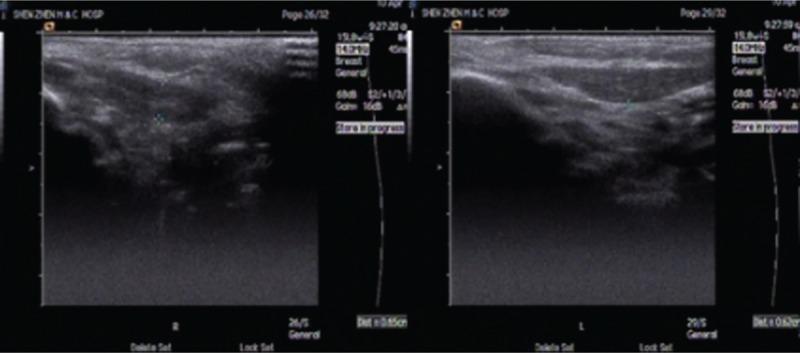

Congenital muscular torticollis (CMT) is a common musculoskeletal abnormality in children, which has been characterized by unclarified pathological changes in the sternocleidomastoid muscle (SCM) and various hypothetical etiologies. There are 2 main hypothetical etiologies for CMT in the literature: 1 infers that CMT may represent the sequela of an intrauterine or perinatal compartment syndrome, and the other regard CMT as a maldevelopment of the fetal SCM.To better understand the etiopathogenesis of CMT, we screened the necks of 1-day-old newborns that may potentially have CMT for evidence of SCM trauma or tumor.A convenience sample of 2564 full-term (>37 weeks) Chinese neonates were included in this study. All neonates were screened for CMT by physical examination at birth. If CMT was suspected, further ultrasonic and physical examinations were performed. When CMT was confirmed, we provided appropriate interventions and follow-up. The progress and changes in patients with CMT were recorded.Following physical examination, 44 of 2564 neonates were diagnosed with suspected CMT based on obvious facial asymmetry or palpable swelling or mass in the SCM. Among these, ultrasound examination showed 81.8% (36/44) had asymmetry in the thickness of the bilateral SCM. The 36 neonates were followed-up for 6 months; among them, 1 infant developed CMT and 35 showed normal development in bilateral SCM. The 1 patient with CMT underwent regular physiotherapy and recovered with no evidence of recurrence after the final 3 years of follow-up. No neonates suffered from signs of neck trauma, such as hematoma or subcutaneous ecchymosis.There was no evidence of neck trauma in this 1 day old newborn. The pseudotumor of SCM that developed after birth underwent differentiation, maturation, and disappeared as the baby grew. The SCM asymmetry did exist in some of the newborn babies, and became symmetric with the baby's growth. Data from this clinical study and our previous ultra-structural pathological studies suggested that both prenatal and postnatal factors play important roles in CMT. We hypothesized that CMT might be a developmental disease.